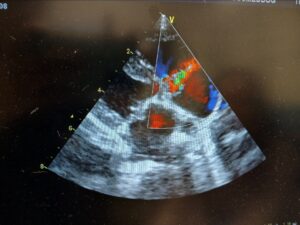

Hello everyone and welcome to my first blog for week 1 of my internship. I headed out to Denver on the 29th to start working on the 30th. On Monday, I got a tour of the building seeing the different departments, cardiology, oncology, surgery, and emergency and critical care. This week, I started in cardiology and I got to learn more about the different heart conditions animals may get like heart murmur and atrial fibrillation. I followed Dr.Julie Martins to see ultrasounds of the heart of cats and dogs.

On Thursday, I got to follow both Dr.Erika and Dr.Lee to see the conversations with clients and hear the discussions on treatments for the animal. Ones of the cases I found interesting to see was that a dog had come in because its lungs were affecting the heart causing high blood pressure around the lungs. This type of case is secondary because another factor outside the heart that is causing a problem. It was interesting because it showed how the clinic works together with other departments and other clinics to get the animal the care it needs. Overall, the first week was amazing and fun and I really enjoyed learning about the heart.